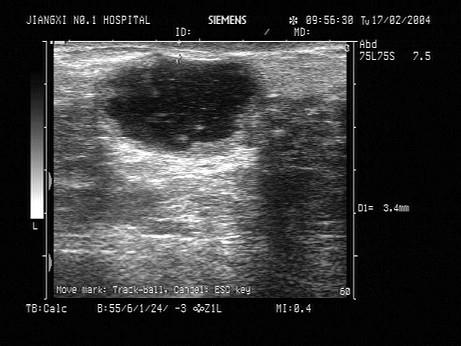

问题 患者,女性,产后,右乳房肿胀,疼痛,红肿,超声见回声不均匀,低回声内见点状回声流动。如图所示考虑为?(?)

选项 A.乳腺囊肿 B.乳腺脓肿 C.乳腺癌 D.乳腺腺瘤 E.纤维瘤

答案 B